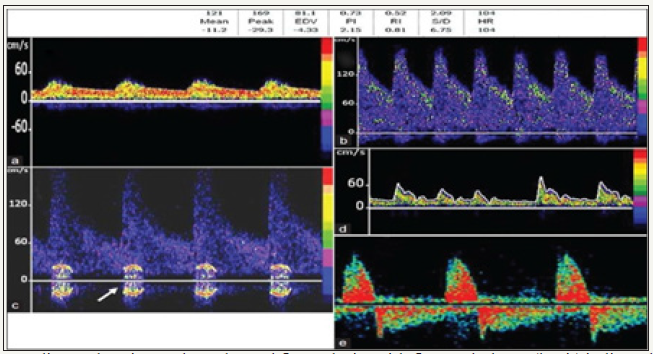

Abnormal spectrum waveforms

Delayed systolic flow acceleration or flattened systolic upstroke and slow diastolic deceleration with end diastolic velocity (EDV) above 50% of peak systolic velocity (PSV) is hallmark of stenosis proximal to the site of PWD this is known as blunted flow, and is due to compensatory vasodilatation distal to the stenosis (Figure 7). Patients with focal intracerebral stenosis/ vasospasm- there will be focal flow acceleration, with increasing stenosis; the increased in the flow creates flow turbulence, represented by bruit, which is seen as symmetrical artefact on either side of baseline.